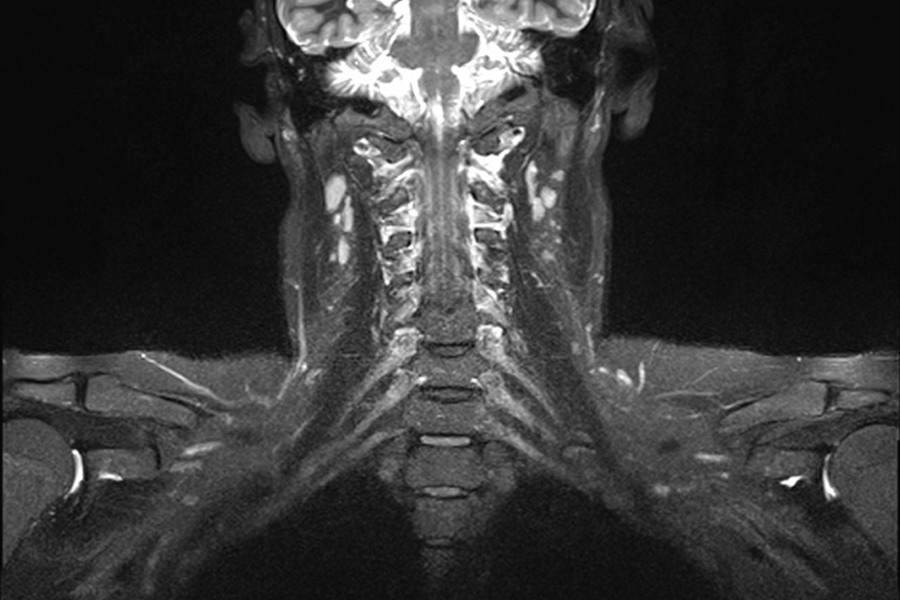

Die Magnetresonanztomographie (MRT) ist ein bildgebendes Verfahren, das mittels starker Magnetfelder und Radiowellen detaillierte Schnittbilder des Körpers erzeugt. Die Methode eignet sich besonders gut für die Untersuchung von Gehirn, Rückenmark und Wirbelsäule, inneren Bauch- und Beckenorganen, sowie von Muskeln und Gelenken. Abgesehen von der Darstellung der Anatomie lassen sich mithilfe der MRT auch funktionelle und dynamische Prozesse, wie etwa Stoffwechselvorgänge im Gehirn abbilden.

- Halsweichteile

Am Zentrum für Radiologie und Neuroradiologie stehen uns Kernspintomographen der neuesten Generation mit 3 Tesla und 1,5 Tesla Feldstärke zur Verfügung. Die Geräte ermöglichen hochauflösende MRT-Untersuchungen aller Körperregionen. Die detaillierten Bilder erlauben es uns, erkrankte Organe erkennen und beurteilen zu können. Gemeinsam mit den Fachabteilungen des Klinikums und den niedergelassenen Spezialisten entwickeln wir dann eine individuelle Therapie für unsere Patientinnen und Patienten.